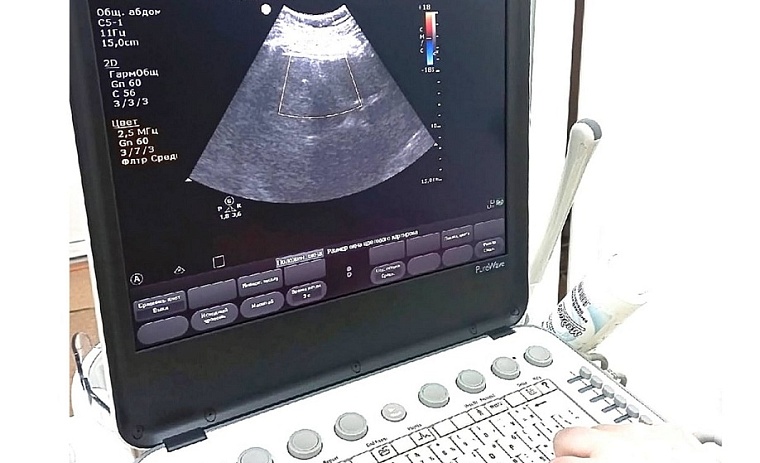

В больнице п. Боровский Тюменской области появилось новое медицинское оборудование. Два современных аппарата УЗИ и маммограф приобрели в рамках модернизации первичного звена здравоохранения.

Оба аппарата УЗИ экспертного класса, один из них портативный, сообщили в пресс-службе администрации Тюменского района. Пять датчиков позволяют проводить исследования в области кардиологии, гинекологии, неонатологии, урологии и многих других, а также выявлять онкозаболевания при помощи эластосонографии.